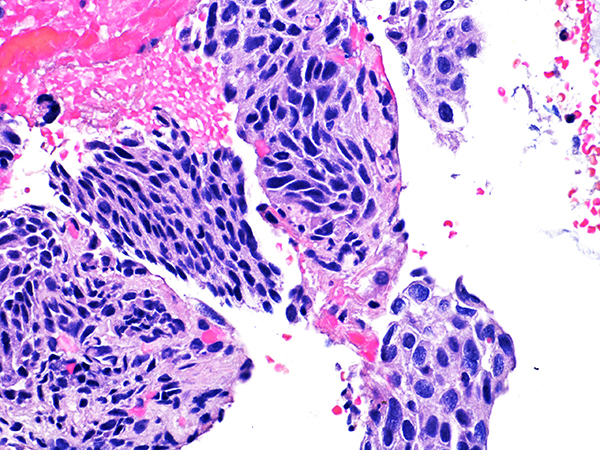

Case 4

Soft Bx CIN 3

40x - High Power |